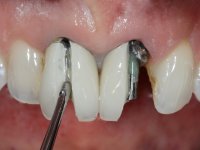

O tratamento iniciou-se com a confeção de moldeiras transparentes em silicone para aplicação de peróxido de carbamida a 16%. Os espaçadores colocados na superfície vestibular foram cuidadosamente preparados em resina nos modelos de gesso. O tratamento foi feito aplicando o produto 2 horas por dia durante 8 dias. Após o branqueamento esperamos 4 semanas e iniciamos o tratamento prostodôntico. Foi realizada uma pré-impressão em silicone para confeção de uma ponte provisória com resina composta de polimerização dual. Em seguida iniciamos a remoção das coroas. Foi feito um corte vertical na zona média da coroa até encontrar a superfície do espigão falso coto fundido. No bordo incisal também foi realizado o mesmo corte. Em seguida com um luxador fino foi feita a separação das partes distais das coroas. Para a remoção das partes mesiais foi feito um corte na linha média abrangendo ambas as coroas. No final da remoção atraumática das coroas antigas os cotos foram re -preparados. Na re-preparação dos cotos a linha de acabamento foi colocada a nível intra-sulcular. Na mesma consulta foi feita a impressão definitiva. O afastamento gengival foi realizado com a técnica da pasta de caolino comprimida pela ponte provisória.  A impressão foi feita pela técnica de dupla mistura com dupla viscosidade com silicone de presa rápida. No laboratório foram confecionadas 2 coroas com infraestrutura em Zr sendo revestidas a cerâmica. No sentido de evitar aparência de coroas “muito altas” foi aumentado ligeiramente o diâmetro mesio-distal sobrepondo-se ligeiramente aos dentes adjacentes. A ponte provisória foi removida os cotos foram polidos e as coroas foram colocadas para verificação final. Confirmado o seu ajuste e aprovadas pela paciente foram cimentadas definitivamente com cimento de ionómero de vidro reforçado com resina.